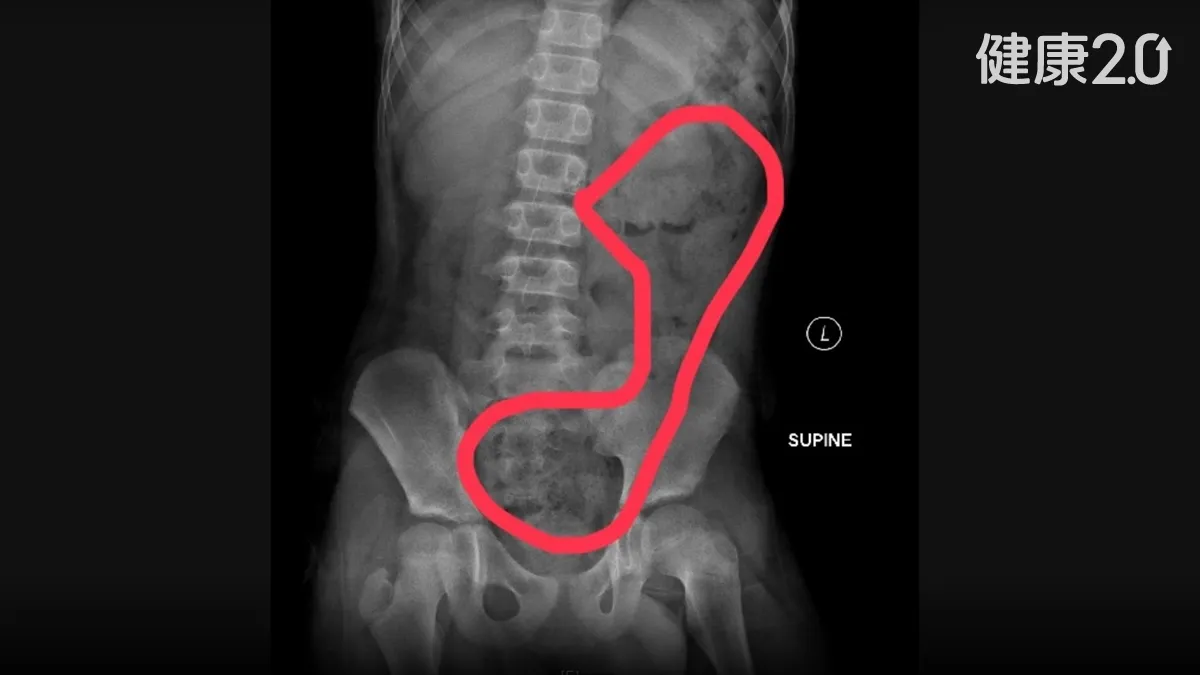

石崇良認為這樣的情況應該改變,透過門診安排住院等待時間比急診長才合理,從健保統計資料可以看出,醫學中心的病人大約有60~70%都不是重大傷病或緊急、罕見、難治、需要手術的病患,造成分級醫療和醫療資源嚴重錯置,石崇良認為這也是大醫院急診總是人滿為患的原因之一。